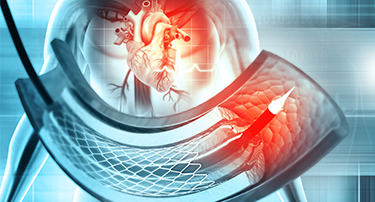

Innovative Heart Valve Solutions That Avoid Open-Heart Surgery

For decades, open-heart surgery was the sole method for repairing or replacing a defective heart valve. Although effective, the old method is marked by giant incisions, extended recovery periods, and jeopardy to elderly or high-risk patients.

TAVI Vs. Open-Heart Surgery: Which Is The Right Choice For You?

For heart valve replacement, patients usually have two primary choices: Transcatheter Aortic Valve Implantation (TAVI) and open-heart surgery. Both involve replacing a faulty aortic valve, but they are very different in approach, recovery period, and applicability to various patient populations. Knowing the main differences, advantages, disadvantages, and success rates can assist you in making an informed choice.

Who Is The Ideal Candidate For TAVI? Understanding Eligibility & Benefits

Transcatheter Aortic Valve Implantation (TAVI) has revolutionized the treatment of severe aortic stenosis, especially for patients who are high-risk candidates for traditional open-heart surgery. This minimally invasive procedure offers a lifeline to many, but determining who stands to benefit the most is crucial.